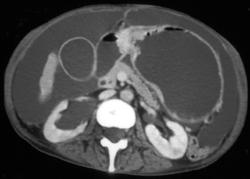

Gastric Adenocarcinoma